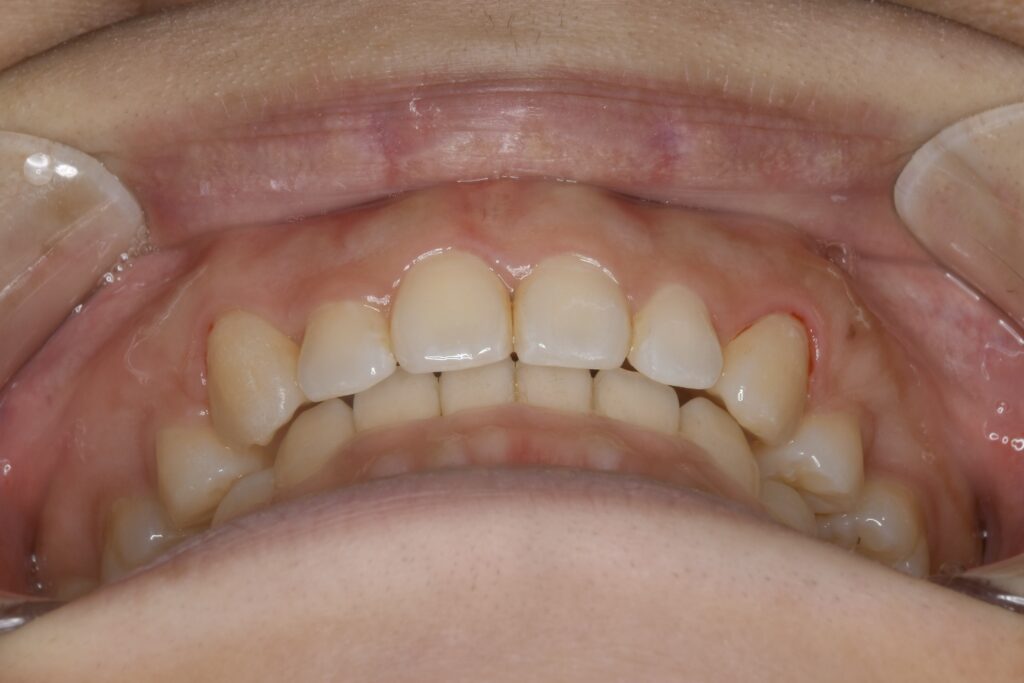

32歳 女性 治療期間:1年7ヶ月

BEFORE

主訴 口元が出ていて気になる。

診断名・主な症状 叢生を伴う上顎前突

治療内容 上下とも歯を2本抜いて、上の前歯を後方に引きながら、でこぼこを治しました。